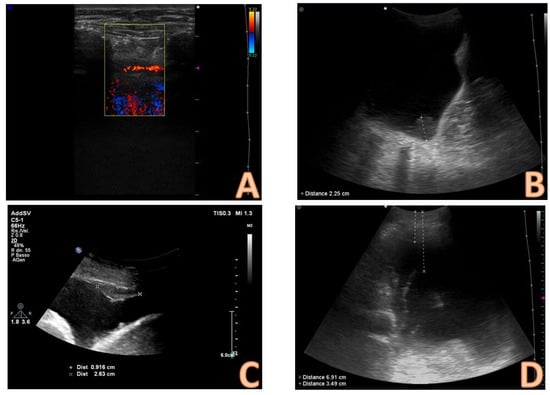

5. The Role of CEUS